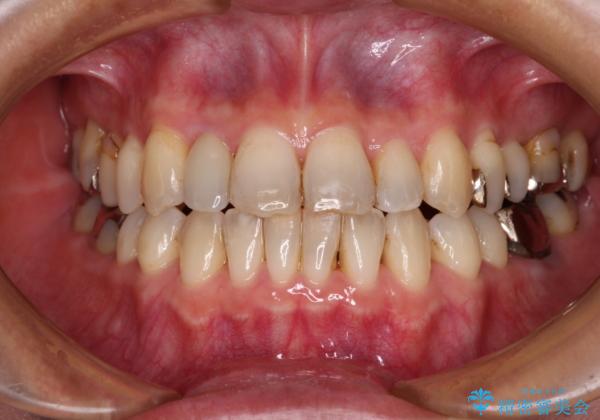

急速拡大装置 前歯の反対咬合をインビザラインで改善

- 前歯の反対咬合を気にして来院された患者様です。

上顎骨の幅が下顎骨よりも小さいので、拡大装置により骨幅を広げて上下関係を改善すると同時にワイヤー矯正で反対咬合の改善を図り、その後インビザラインにて歯並びを整えることとしました。

上顎前歯の矮小歯は矯正治療の途中でオールセラミッククラウンを装着し、左右のバランスを整えることとしました。

急速拡大装置の使用により奥歯の咬み合わせが劇的に変わり、その変化を利用して反対咬合を改善することができました。

治療期間中は奥歯が咬み合わず、食事が取りにくいなどの不都合がありましたが、最終的にはきれいに整えることができました。